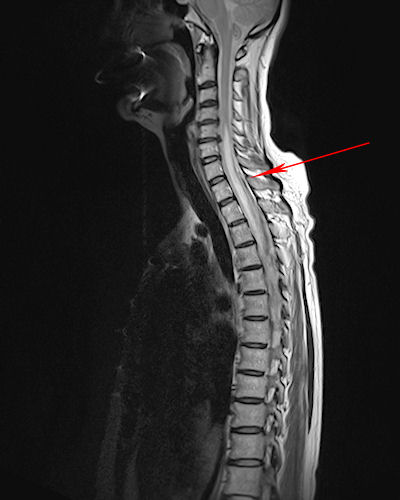

Case 1

Case 2

Case 3

Case 4

Case 5

Case 6

Case 7

Case 8

Case 9

Case 10

Case 11

Case 12

Case 13

Case 14

Case 15

Case 16

Case 17

Case 18

Case 19

Case 20

Case 21

Case 22

Case 23

Case 24

Case 25